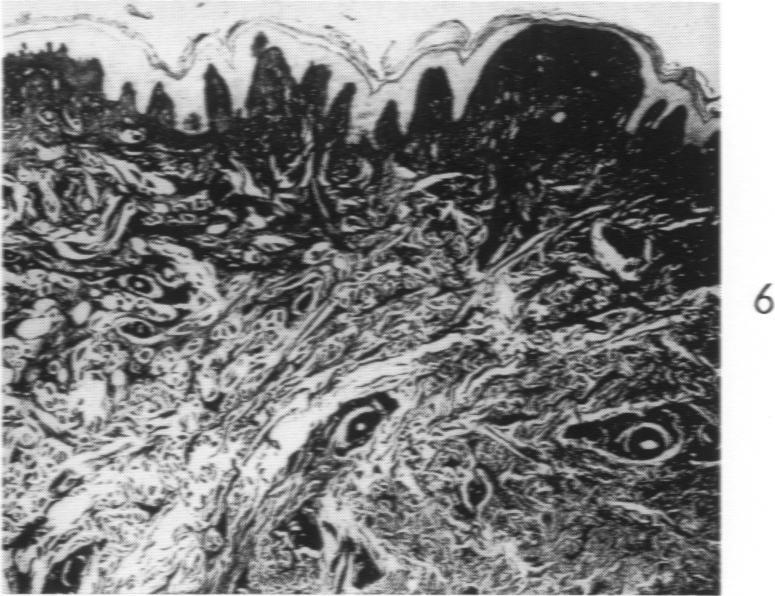

Lipoid Proteinosis (Lipoglycoproteinosis): A Histochemical Study of Two Cases.

Am J Pathol. 1962 May;40(5):599-613.